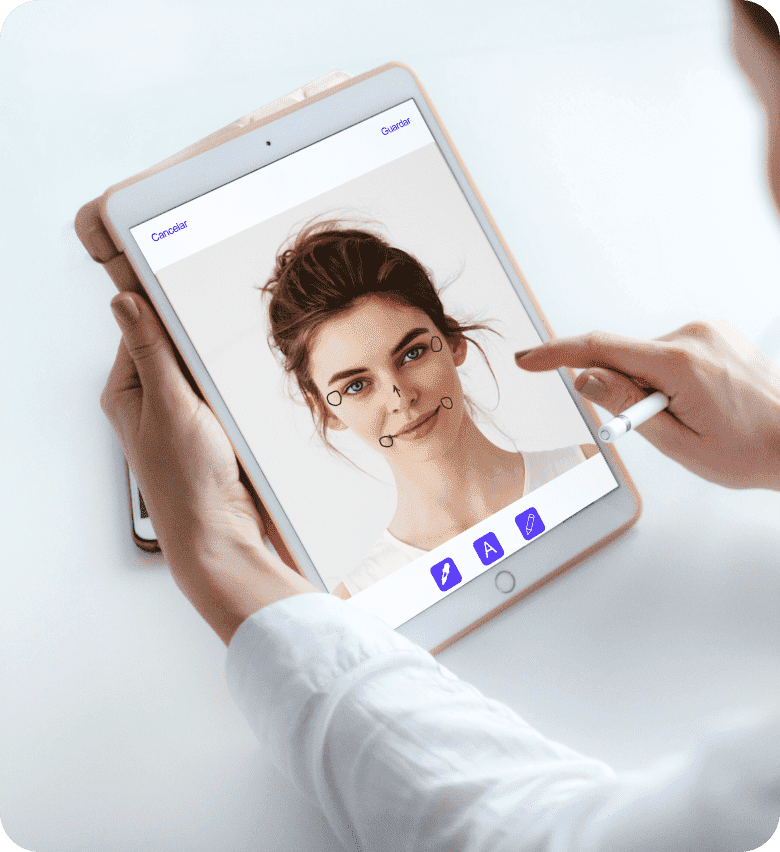

Gestiona fácilmente todos los procesos de tu clínica, apoyándote en herramientas digitales desarrolladas desde la visión del médico, como una completa historia clínica, fotografías y anotaciones de seguimiento, trazabilidad de stock, firma digital y marketing de seguimiento.